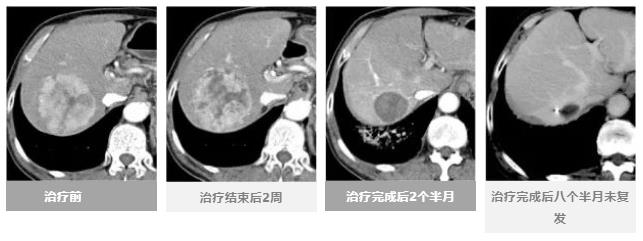

治疗效果进度